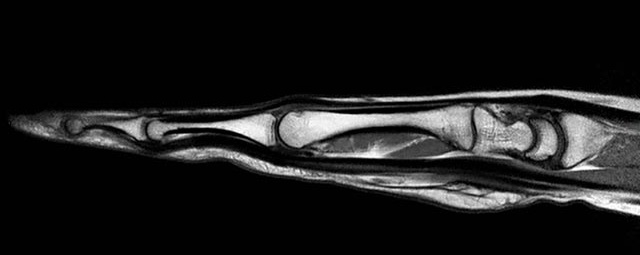

- Beurteilung von Knochen, Bändern und anderen Weichteilstrukturen der Gelenke nach Unfall.

- Arthrosediagnostik (Knorpelschaden)

- Impingement-Symptomatik

- Ursachenklärung bei wiederholter spontaner Gelenkluxation

- Ausbreitungsdiagnostik bei Gelenkentzündung, z.B. im Rahmen von rheumatischen Grunderkrankungen

- MR-Arthrographie – nach örtlicher Betäubung und gründlicher Desinfektion der Haut wird unter Lagekontrolle mit Röntgen-Durchleuchtung eine kleine Nadel in den Gelenkraum positoniert und darüber ein MR-taugliches Kontrastmittel in den Gelenkraum gespritzt. Danach wird die Nadel entfernt. Anschließend erfolgt die MRT des Gelenkes. Diese Methode stellt kleine anatomische Strukturen des Gelenkraumes verbessert dar, z.B. zur Therapieplanung vor Arthroskopie bei Sportverletzungen der Schulter oder Gelenkinstabilität.